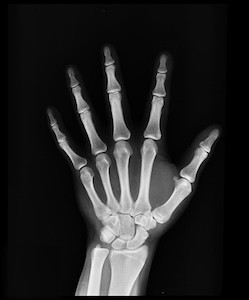

When you think about staying healthy, you probably consider lifestyle changes to prevent conditions like cancer and heart disease. Keeping your bones healthy to prevent osteoporosis may not be at the top of your list, but it should be. Some people think of bones as hard and lifeless. They're living, growing tissue. Bones are made up of three major parts that make them flexible and strong. It’s never too late, at any age, to take steps to protect your bones!